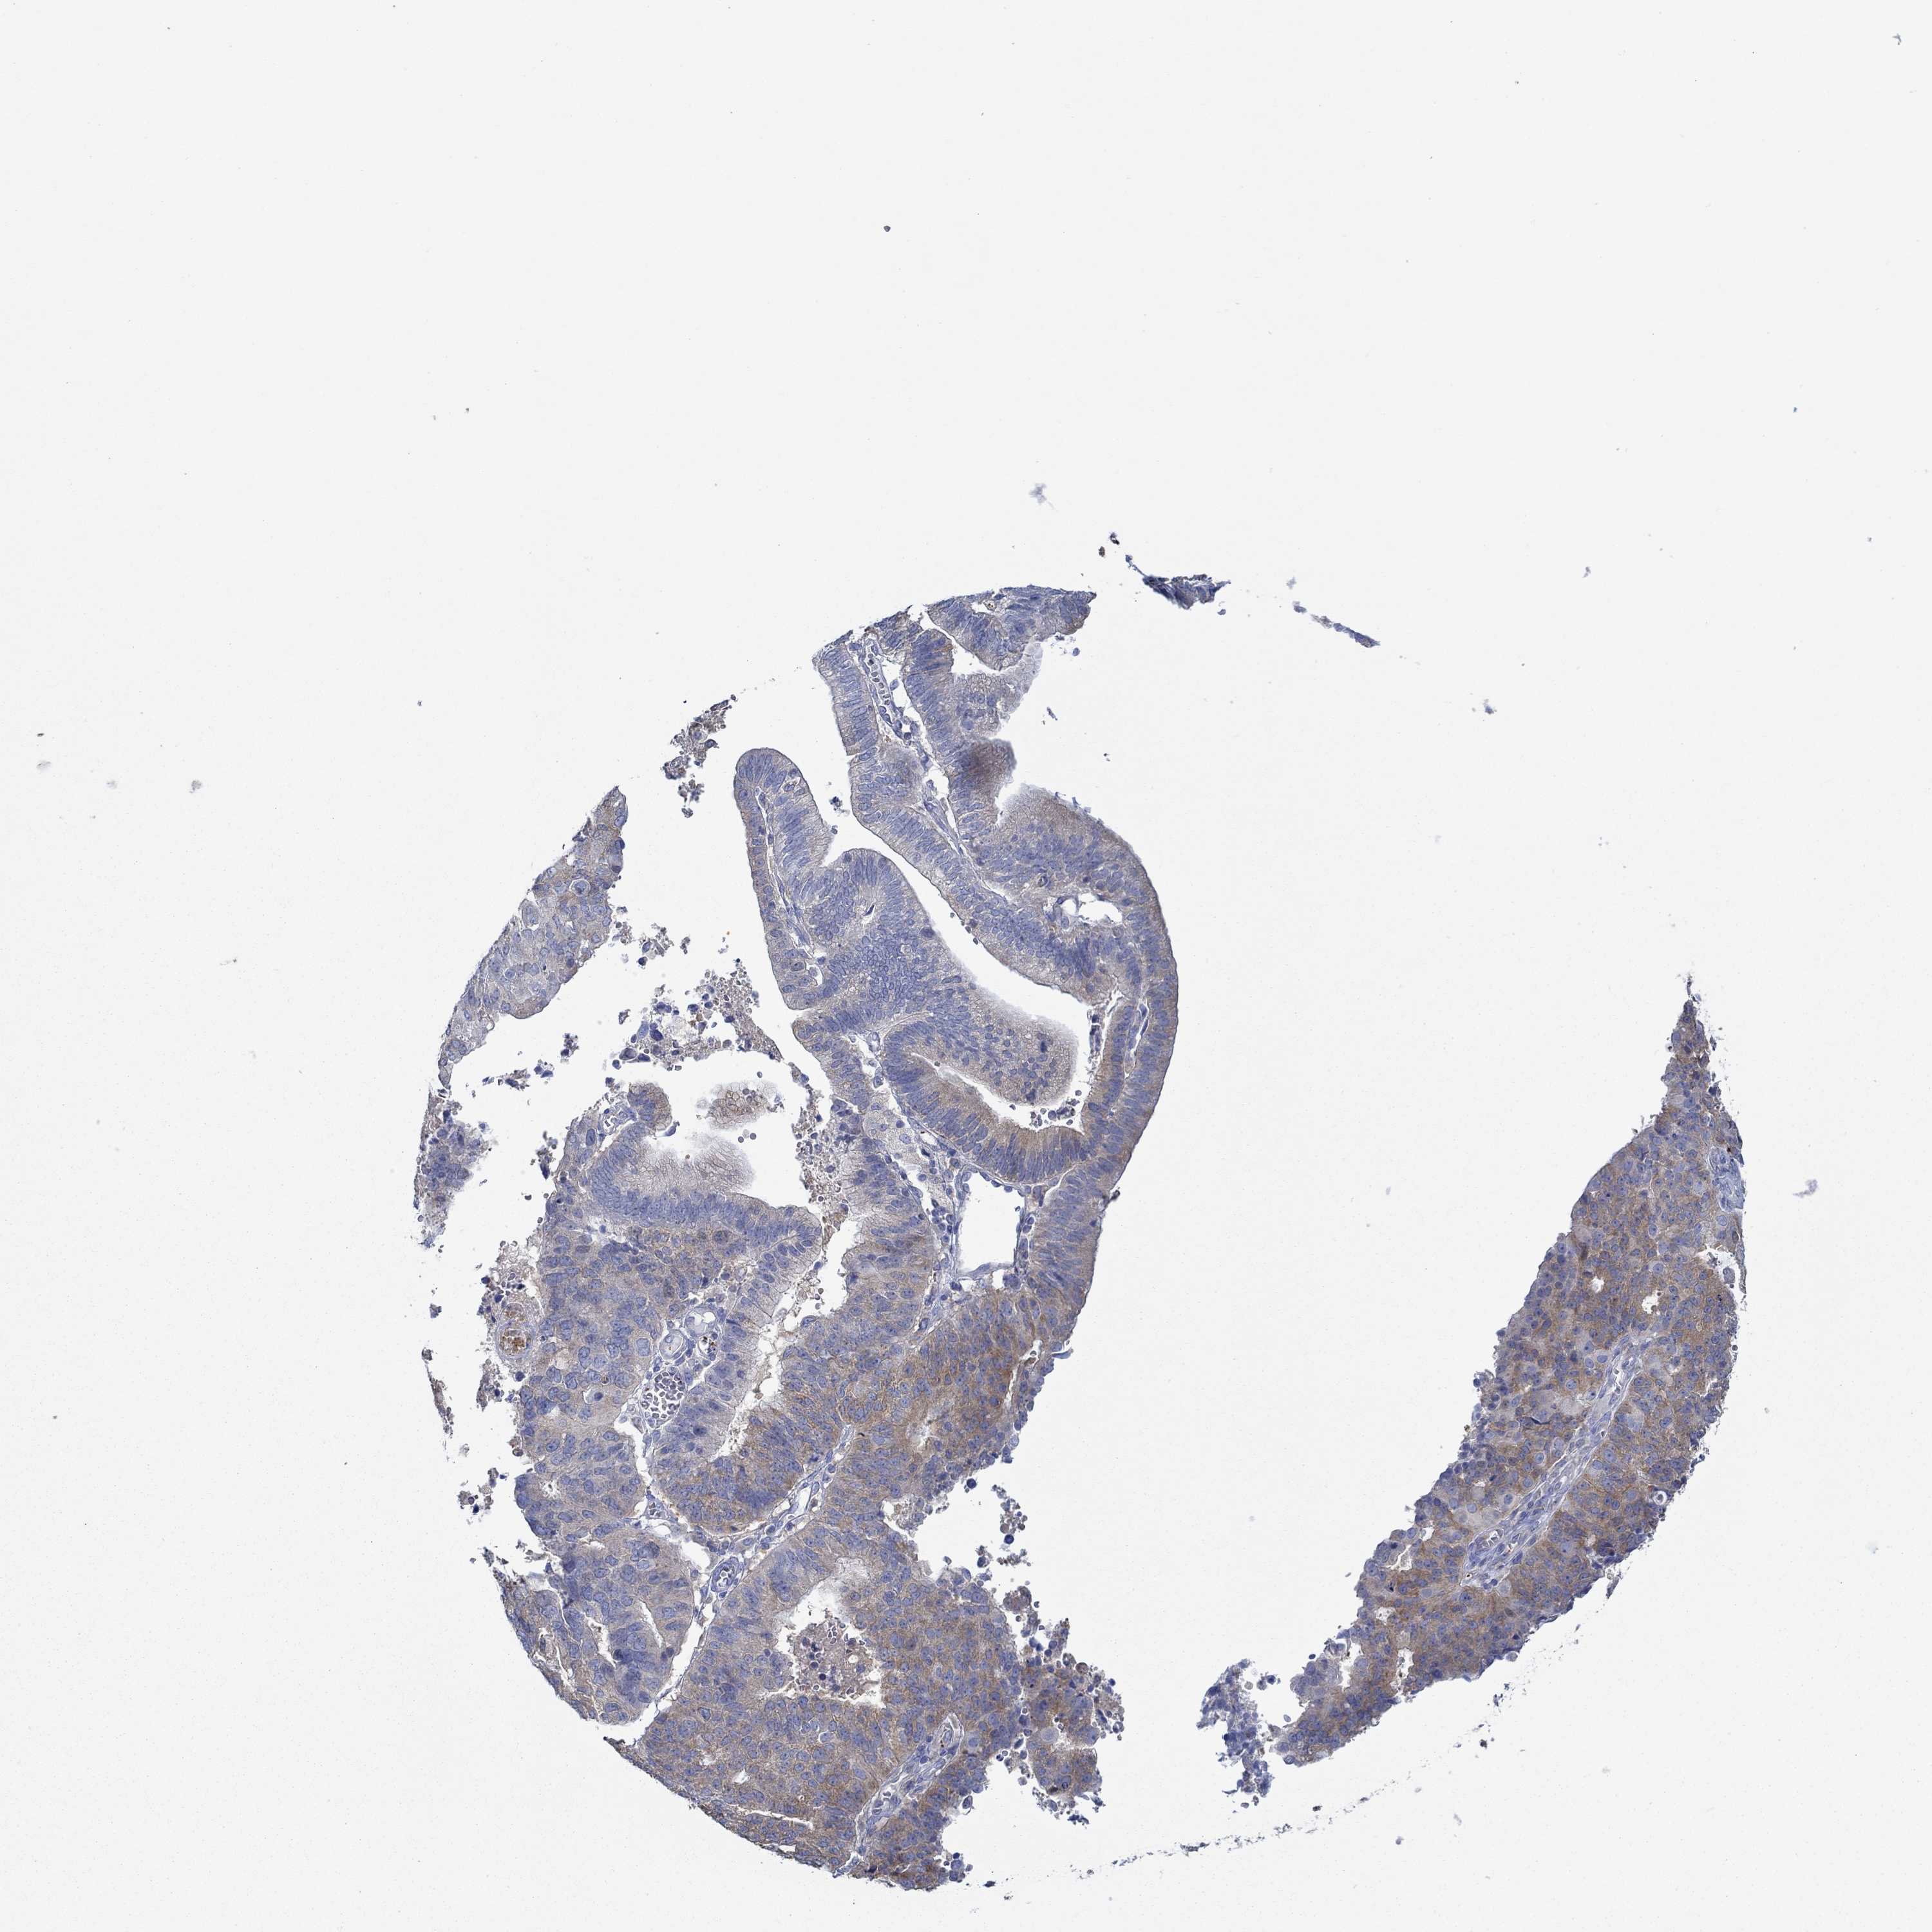

ENDOMETRIAL CANCER - Protein expressioni

A mouse-over function shows sample information and annotation data. Click on an image to view it in a full screen mode. Samples can be filtered based on level of antibody staining by selecting one or several of the following categories: high, medium, low and not detected. The assay and annotation is described here.

Note that samples used for immunohistochemistry by the Human Protein Atlas do not correspond to samples in the TCGA dataset.

Antibody stainingi

Antibody staining in the annotated cell types in the current human tissue is reported as not detected, low, medium, or high, based on conventional immunohistochemistry profiling in selected tissues. This score is based on the combination of the staining intensity and fraction of stained cells.

Each image is clickable and will lead to virtual microscopy that enables deeper exploration of all samples and also displays staining intensity scores, fraction scores and subcellular localization as well as patient and tissue information for each sample.

Antibody HPA067508

Antibody CAB080514

Antibody CAB080517

Staining

High

Medium

Low

Not detected

Intensity

Strong

Moderate

Weak

Negative

Quantity

>75%

75%-25%

<25%

None

Location

Nuclear

Cytoplasmic/membranous

Cytoplasmic/membranous,nuclear

Adenocarcinoma, NOS

Adenocarcinoma, metastatic, NOS